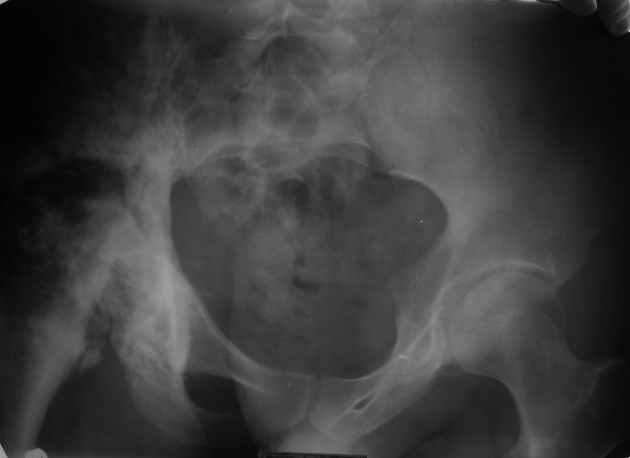

Уважаемые коллеги! Парень 28 лет, болен ангиосаркомой в течении 12 лет.

Лечился радио-, химиотерапией. На сегодня конечность неопорная, болевой синдром. Жизнь проходит в постельном режиме, лечение направлено на её продление. В головных и региональных клиниках России расценивают ситуацию, как достойную лишь консервативного паллиатива. Возможно ли в такой ситуации лечение, кроме радио- и химиотерапии, хотя бы улучшающее качество жизни? Чем могут помочь зарубежные клиники? Dear colleagues! The guy of 28 years, is sick with angiosarcoma of pelvis during 12 years. He was treated with radio-, chemotherapy. For today there are limb not basic, a painful syndrome. Life passes in a bed, treatment is directed on its prolongation. In head and regional clinics of Russia regard a situation, as worthy only for conservative palliative treatment. Is it possible treatment, except for radio and the chemotherapy, improving quality of life in such situation? Can foreign hospitals offer the help?

Общее состояние удовлетворительное. Режим постельный. В сознание, контактен. Беспокоят боли в правой половине таза, неопорность правой конечности.